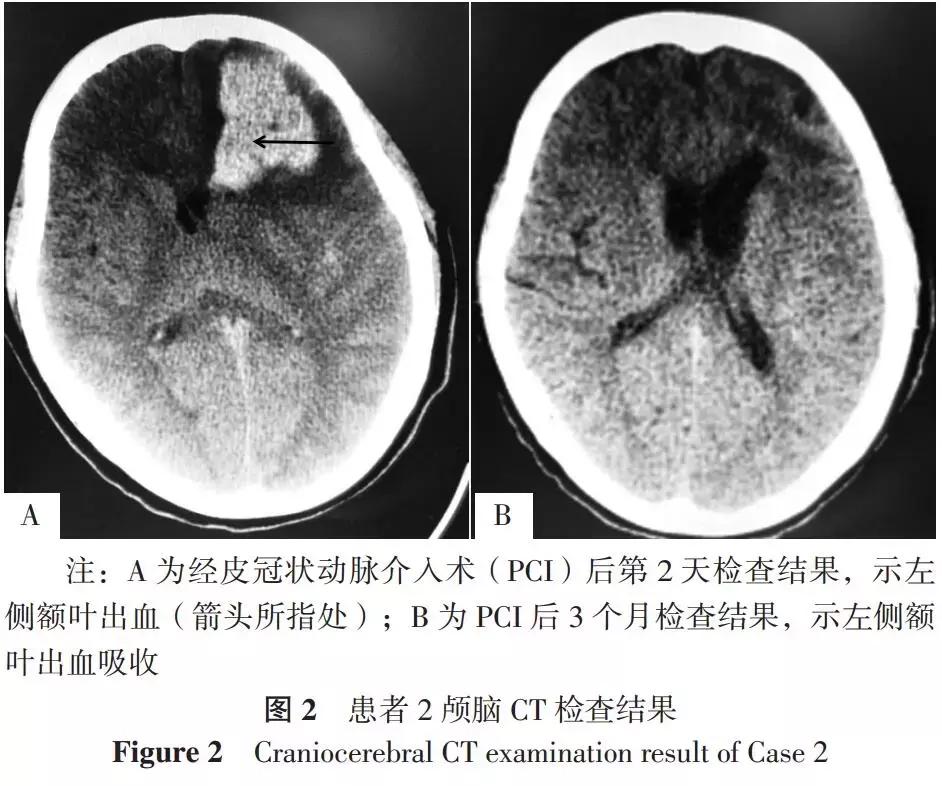

患者2,女,61岁,因“头晕半年,加重伴胸闷1个月”于2017-02-06入住广东省中医院。患者既往有高血压病史。入院诊断:头晕和眩晕(原因待查)、冠心病(待排除)、高血压3级(很高危),遂给予阿托伐他汀调脂、稳定斑块,阿司匹林抗血小板聚集,琥珀酸美托洛尔、培哚普利叔丁胺片逆转心肌重构,甲磺酸倍他司汀片改善眩晕症状等。患者2017-02-14行冠状动脉造影发现右冠状动脉近中段长狭窄,最大狭窄率约为85%,遂于右冠状动脉中段连续植入3.00 mm×24.00 mm、3.50 mm×28.00 mm支架2枚,PCI*共中**使用普通肝素8 000 U。患者于PCI后第1天凌晨出现呕吐,第2天出现对答欠合理、二便*禁失**,急查颅脑CT发现左侧额叶出血(见图2A),出血量约为63 ml;遂暂停抗栓治疗并给予减轻脑水肿、促进神经功能恢复、保护胃黏膜治疗等。患者PCI后第3天复查颅脑CT发现左侧额叶出血无明显改善,第8天复查颅脑CT发现出血较前吸收,第16天行血栓弹力图(TEG)发现血栓形成的最大幅度(MA)增大,遂加用氯吡格雷抗血小板聚集,后患者病情稳定出院,PCI后3个月复查颅脑CT示左侧额叶出血吸收(见图2B),随访1年恢复良好,未发生缺血或出血事件。